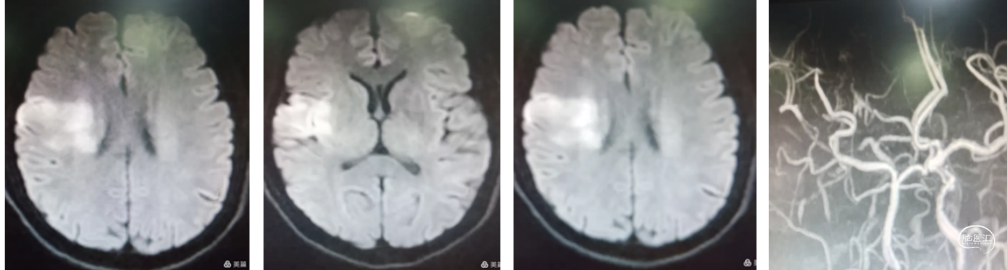

入院后急查CT未见出血和低密度改变。核磁DWI示:左侧大脑半球梗塞,左侧大脑中动脉和内囊区域受累。MRA示:左侧颈内动脉未显影,考虑闭塞。

造影示:左侧颈内动脉起始部以远未向远端供血,左侧颈总动脉呈火苗样窜动。查询颈内动脉造影颈内动脉血流火苗样迟滞窜动。

8Fguiding到达C1段支撑070银蛇中间导管裸奔边上行边抽吸,抽出部分血栓,造影显示到血流达到C6段。

术中边推进导管边抽吸,抽出部分血栓,造影显示到血流达到C6段。